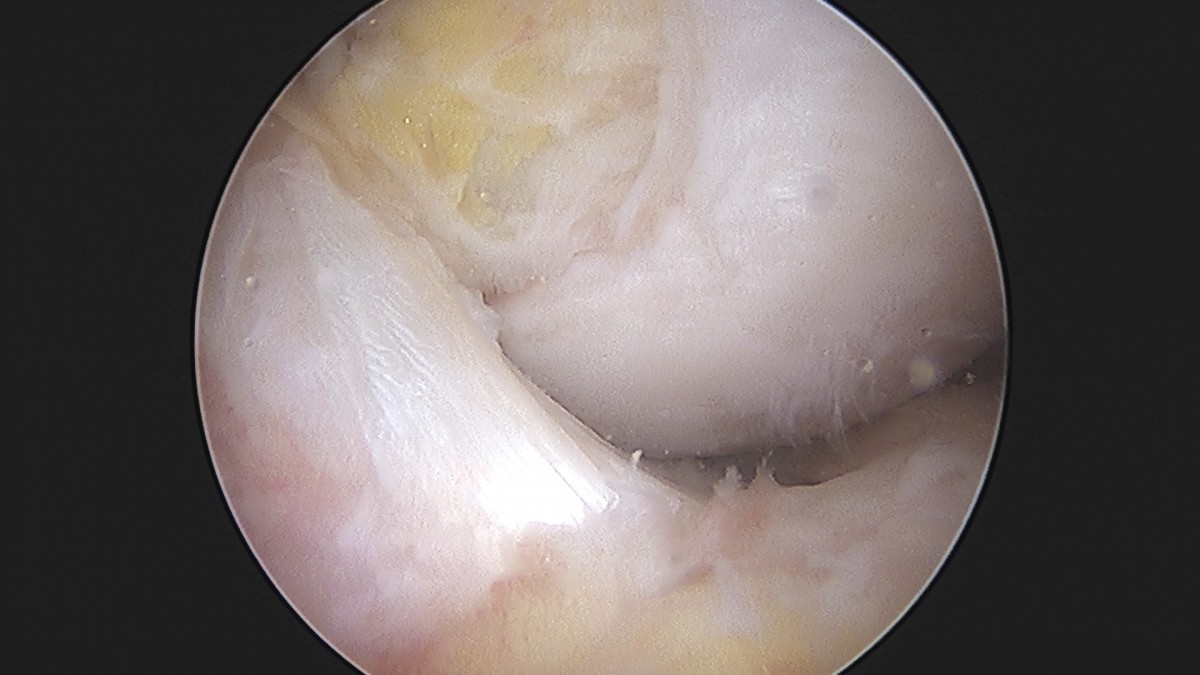

이재상원장님 무릎 반월상 연골판 절제술 장영O 환자

작성자 최고관리자 댓글 0건 조회 369회 작성일 25-09-16 16:02

dae765e4d9ac96aee867c9d6292d8784_1758006136_1236.jpg